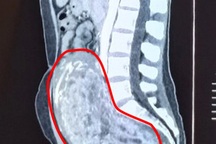

Kết quả thăm khám tại Bệnh viện Ung Bướu Hà Nội cho thấy bệnh nhân có khối u ở thận trái kích thước khoảng 15x20cm, phá hủy hoàn toàn cấu trúc nhu mô thận, xâm lấn đài - bể thận. Đáng chú ý, khối u đã gây huyết khối trong tĩnh mạch thận, lan tới tĩnh mạch chủ dưới, làm tăng nguy cơ tắc mạch hoặc thuyên tắc mạch phổi đe dọa tính mạng.

Hình ảnh chụp CT khối u ở thận xâm lấn tĩnh mạch chủ dưới (Ảnh: Bệnh viện cung cấp).